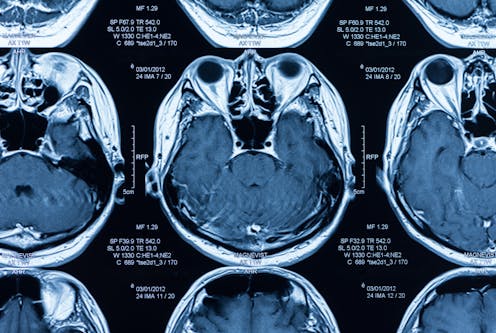

A tool that can help is an electroencephalogram, or EEG, which tests brain waves. Functional brain imaging, such as functional MRI, is another tool used to gain more insight into what is going on inside a brain by monitoring the change in activity of certain areas, especially, if no such “simple commands” can be executed.

In the recent study published in the New England Journal of Medicine, neurointensive care physicians – doctors who take care of patients with brain injury in intensive care – and researchers took brain wave analysis to the next level. They connected unresponsive patients with acute brain injury to continuous EEG, and asked them to perform simple commands while their brain waves were being recorded. The EEG data then were fed into a machine-learning algorithm derived from healthy volunteers, which compared the change in brain activity from the state while at rest to the activity recorded following the commands.

Consciousness is much more than what we humans are able to detect with our bare eyes, even for seasoned experts. Combined with a technology that is five years short of celebrating its 100th birthday since the first EEG recording in 1924, artificial intelligence has demonstrated its potential to enhance the yield of EEG in illuminating the black box of the brain.